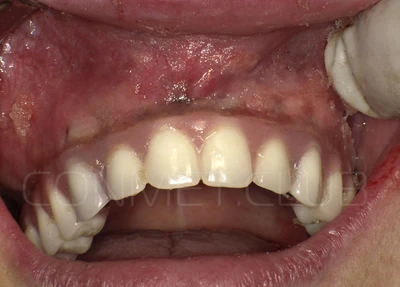

Новые, искусственные зубы фиксируются к этому имплантату стандартными, трансокклюзионными винтами на 1-14 день (в данном клиническом случае на 5 сутки) и по существу являются несъемными!

И в-четвертых: небольшой фрагмент из операции по восстановлению всех утраченных зубов на верхней челюсти. По сути эта операция полностью повторяет протокол и этапность операции представленной в первой части статьи, за исключением того, что искусственные зубы были зафиксированы сразу после операции. Со слов самой пациентки, процесс жевания был совершенно безболезненным с самого первого дня.

Результаты проведенных в 2017-2018 году операций субпериостальной имплантации показали их высокую эффективность, очень быструю адаптацию пациентов к новым зубам и отсутствие послеоперационного болевого синдрома. Интересной особенностью является труднодиагносцируемая, но точно присутствующая микроподвижность имплантатов спустя 6-12 месяцев. Учитывая данную особенность надо категорически избегать объединения субпериостальных имплантатов с естественными зубами или внутрикостными имплантатами!